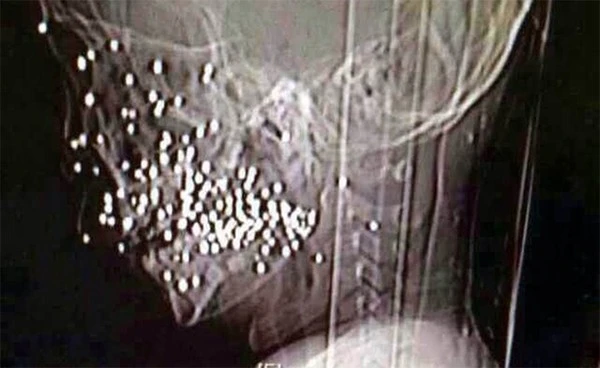

Hình chụp X-quang khuôn mặt bị đạn găm vào của cậu bé.

Được biết, vào thứ Ba ngày 19/8, tai nạn bất ngờ diễn ra khi cậu bé lấy khẩu súng săn của gia đình ra chơi và vô tình bắn vào mặt mình. Ngay lập tức cậu được chuyển tới một bệnh viện ở thành phố Hợp Phì, tỉnh An Huy cấp cứu nhưng sau đó tiếp tục được chuyển tới Bệnh viện Nhân dân số 9 Thượng Hải vào ngày 20/8 để được điều trị chuyên sâu hơn.

Tại đây, các bác sĩ đã gắp bỏ tổng cộng 86 viên đạn găm ở mặt cậu bé và phẫu thuật chỉnh sửa lại xương ổ răng bị vỡ. Hiện cậu bé đang trong quá trình ổn định nhưng vẫn cần phải tiếp tục điều trị trong thời gian sắp tới.